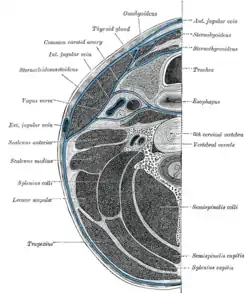

Left scapula. Dorsal surface. Section of the neck at about the level of the sixth cervical vertebra.

Section of the neck at about the level of the sixth cervical vertebra. Muscles of the neck. Lateral view.